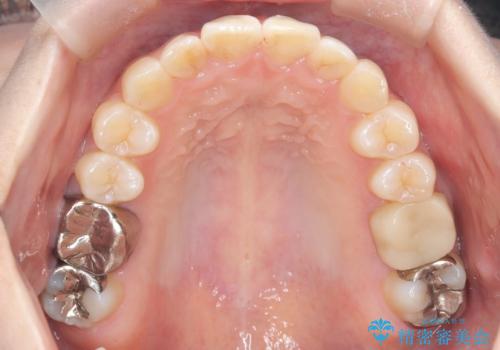

前歯のガタつきをマウスピース矯正で改善

- 前歯のガタツキが気になると来院されました。

奥歯の噛み合わせは綺麗に噛んでいたため、前歯の叢生(でこぼこ)に集中して治療するように計画しました。